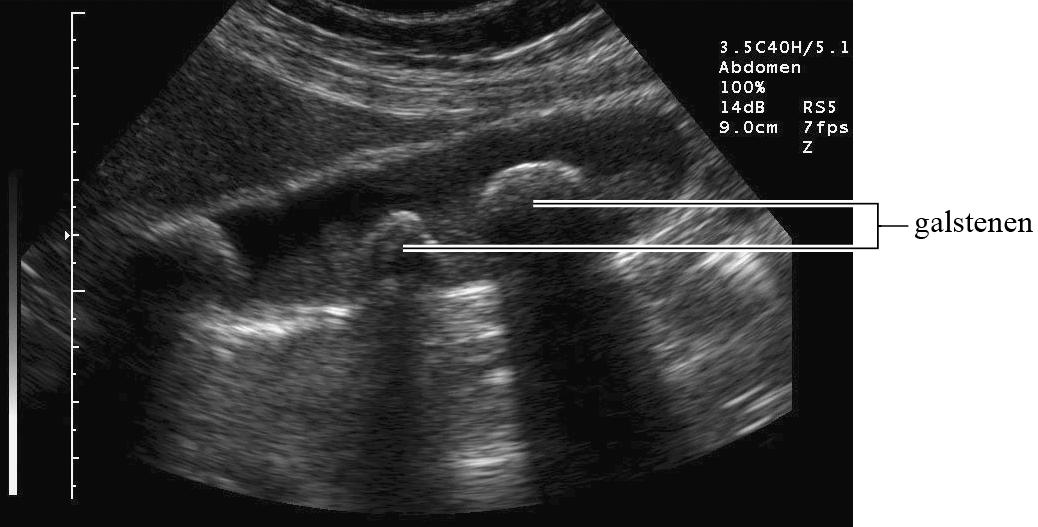

Met behulp van echografie wordt een afbeelding gemaakt van weefsel onder de huid. Zie figuur 1 en 2.